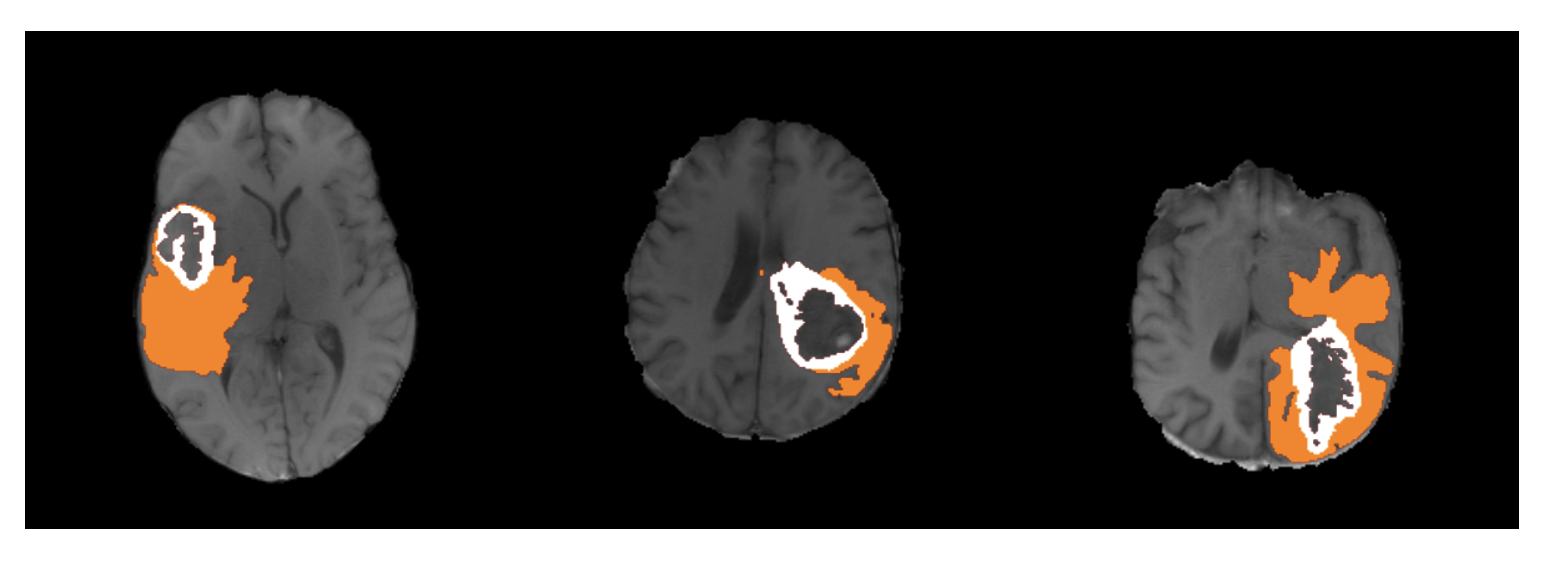

Refer to caption

Figure 4: Visualization of the segmentation results from the ensembled BiTr-Unet for three cases in BraTS2021 Validation data.

3.2 Segmentation Result

During the validation phase, the segmentation images of BraTS2021 validation data from our BiTr-Unet are evaluated by the BraTS2021 organizer through the Synapse platform (https://www.synapse.org/#!Synapse:syn25829067/wiki). We validate three checkpoints with different numbers of trained epochs and also validate the ensemble model of these three checkpoints. Table 1 shows the mean score on the validation data. Fig. 4 presents the segmentation results from the ensembled model for three validation cases.